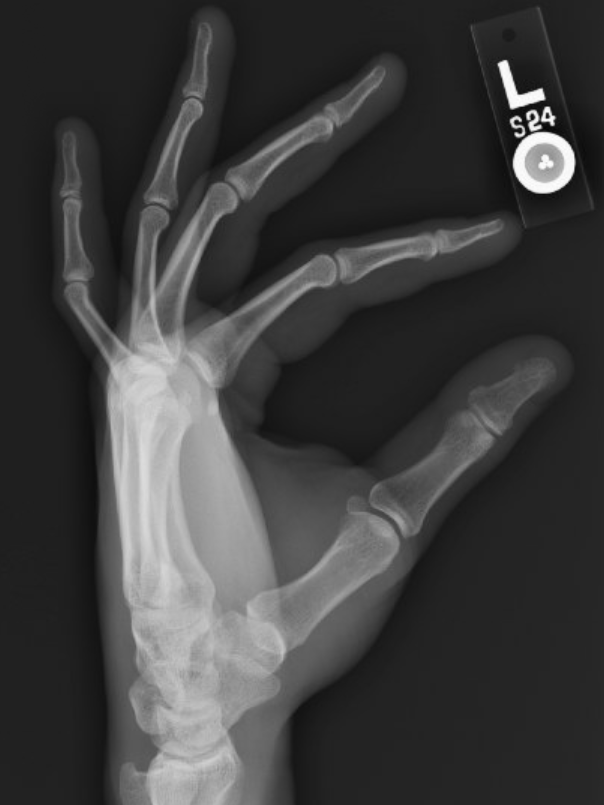

Post-reduction images: